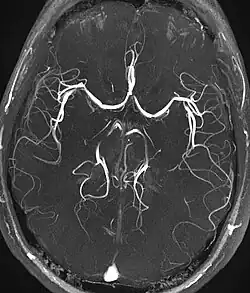

Angiograma de MR em doença cardíaca congênita.

Angiografia por ressonância magnética

A angiografia por ressonância magnética (MRA) gera imagens das artérias para avaliá-las para estenose (estreitamento anormal) ou aneurismas (dilatação da parede vascular, em risco de ruptura). O MRA é frequentemente usado para avaliar as artérias do pescoço e do cérebro, a aorta torácica e abdominal, as artérias renais e as pernas (chamado de "escorrer"). Uma variedade de técnicas podem ser usadas para gerar as imagens, como a administração de um agente de contraste paramagnético (gadolínio) ou usando uma técnica conhecida como "aprimoramento relacionado ao fluxo" (por exemplo, sequências de tempo de voo 2D e 3D), onde a maior parte do sinal em uma imagem é devido ao sangue que recentemente se mudou para esse plano. As técnicas que envolvem acumulação de fase (conhecida como angiografia por contraste de fase) também podem ser usadas para gerar mapas de velocidade de fluxo com facilidade e precisão. A venografia por ressonância magnética (MRV) é um procedimento similar que é usado para imagens de veias. Neste método, o tecido agora está excitado inferiormente, enquanto o sinal é recolhido no plano imediatamente superior ao plano de excitação - criando assim o sangue venoso que recentemente se moveu do plano excitado.[52]